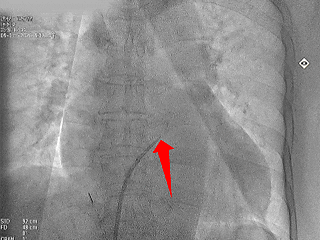

术中DSA肝位造影

心耳呈菜花状,梳状肌发达

心耳内无血栓

开口32.2mm,深度超过22.4mm